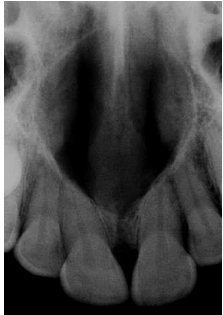

Um paciente do gênero masculino, 39 anos de idade, procurou tratamento odontológico queixando-se de fortes dores na hemiarcada superior. A dor tinha característica difusa, espontânea que piorava em decúbito. O exame clinico revelou presença de restaurações fraturadas com cárie secundária nos elementos 14 e 13, e presença de lesão cariosa profunda no 15. Durante os exames complementares, observou-se que o dente 14 e 13 responderam com dor forte de curta duração após a remoção do estimulo a frio, no entanto o dente 15 respondeu mais intensamente com declínio lento. Não houveram respostas dolorosas quanto aos testes de percussão e palpação.